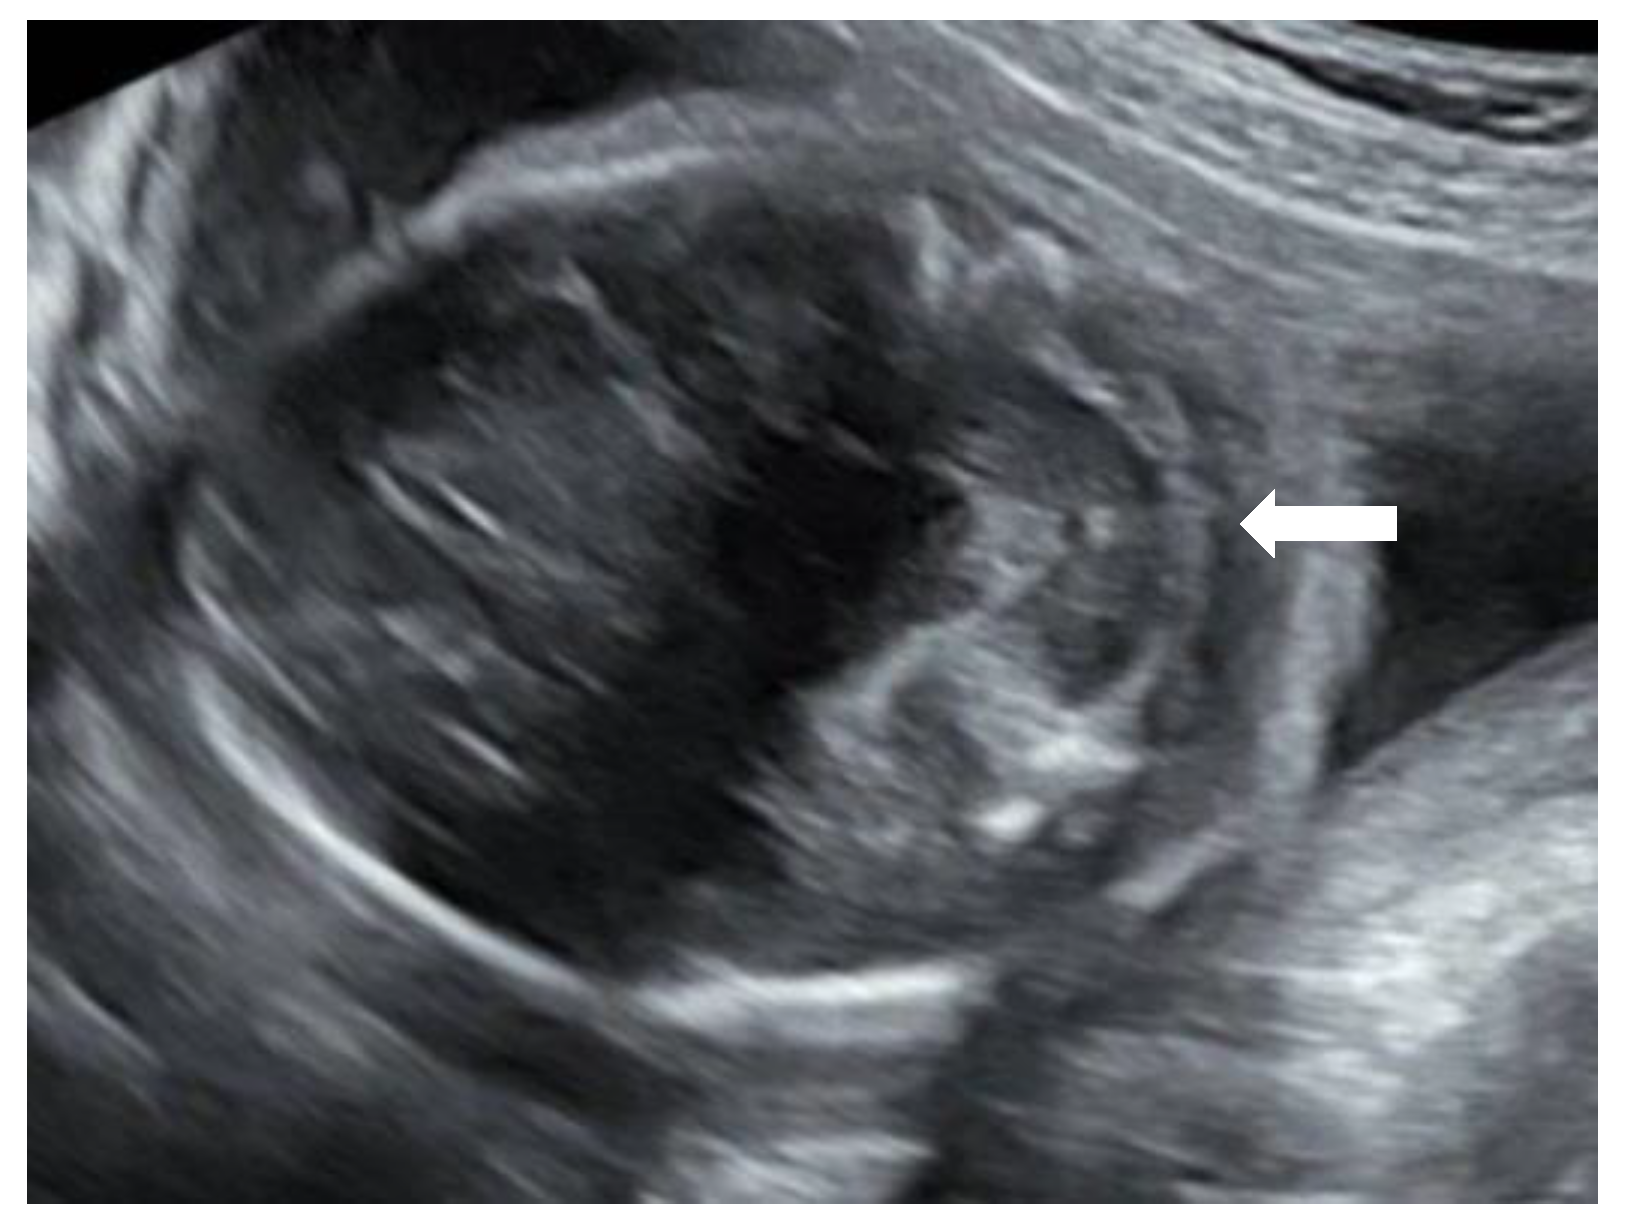

Figure 2). The lateral ventricles were not dilated. Ultrasound examination of the spine revealed a closed skin except for a minimal fistula in the sacro-coccygeal region (

Figure 3,

Figure 4 and

Figure 5). Furthermore, an abnormal gap between the second and third digit was seen on both hands as well as a syndactyly between the first and second toe. Cardiac sonography was normal at both 17- and 24-weeks GA, with a normal four-chamber view, outflow tracts, and three-vessel view. An amniocentesis was performed to rule out genetic anomalies and to measure alfa 1-fetoprotein. Additionally, a fetal MRI was carried out mainly to assess the fetal spine, as the cerebral findings all indicated the presence of an open neural tube defect. MRI analysis confirmed the hydroureteronephrosis as well as the lemon-shaped skull, Arnold–Chiari malformation 11mm below the foramen magnum, absent cerebrospinal fluid around the cerebellum, and possible mild tethering of the cord. However, MRI failed to demonstrate an open spina bifida or any skin defects. The Alfa 1-fetoprotein was elevated, further reinforcing the assumption of a classic spina bifida. QF-PCR showed no aneuploidy for chromosomes 13, 18, 21, X, or Y, but SNP array demonstrated a terminal multiplication of approximately 56 Mb of the long arm (3q23qter) of chromosome 3: arr 3q23q29(141903905-197845233)x2~4. The nature of the multiplication could not be deduced. Interphase FISH with probes in chromosomal regions 3q26 and 3q27 showed 4 copies of both chromosomal bands in approximately 50% of the interphases. Metaphase FISH proved that the 2 extra copies were located on a marker chromosome. Chromosomal examination of the parents showed no anomalies, demonstrating that the aberration occurred de novo in the fetus. Note, a genome-wide NIPT analysis on a blood sample taken at 27 weeks GA failed to detect this anomaly despite its size, indicating this to be a true fetal mosaicism of type 5 (TFM5).